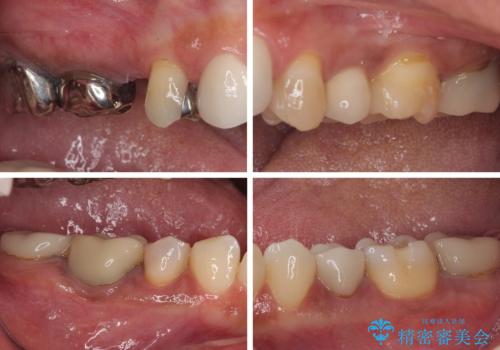

上顎前歯の根尖病変に痛みがありましたが、既に前歯が補綴治療済みであっため、外科的歯内療法(歯根端切除術)を行うことで解決することとしました。

新幹線で通院をされていたため、極力診療回数を減らして、一度にまとめて多くの処置を行うことで負担を軽減しました。